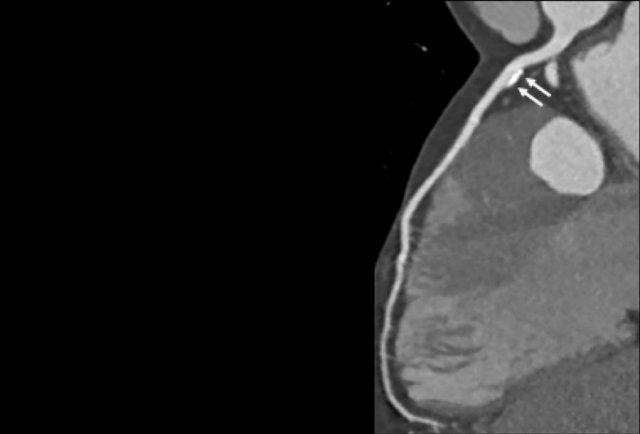

Same patient.

A: Curved MPR of the LAD with non-calcified plaque causing moderate (50-69%) stenosis.

B: The so-called “spider-view” (LAO caudal) of the heart with a 70% stenosis in the proximal LAD. Note the presence of SA nodal artery arising from the proximal LCX and coursing to posterior direction.

C: A drug eluting stent (DES) was implanted into the proximal LAD with good results.